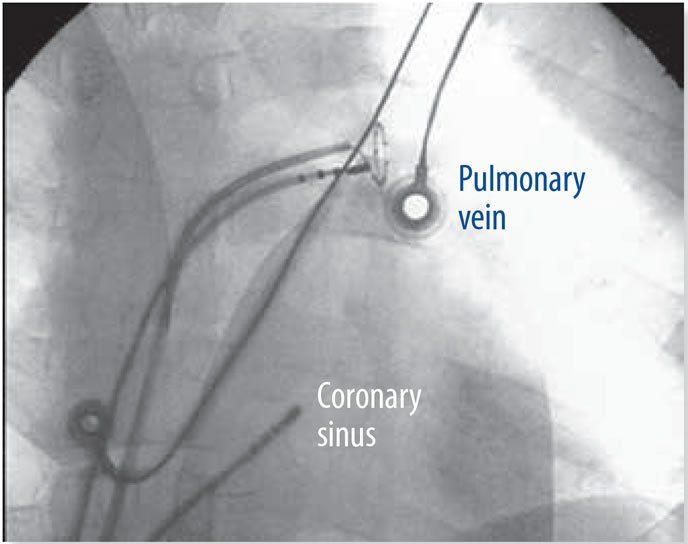

Using catheter ablation to treat atrial fibrillation (Afib) in patients who also have heart failure is more effective than using the antiarrhythmic drug amiodarone (Pacerone, Cordarone), according to a study presented earlier this year at the American College of Cardiologys annual meeting. The study found that ablation reduced the recurrence of Afib episodes better than amiodarone, and reduced the rates of hospitalizations and mortality more effectively than the widely used Afib drug.